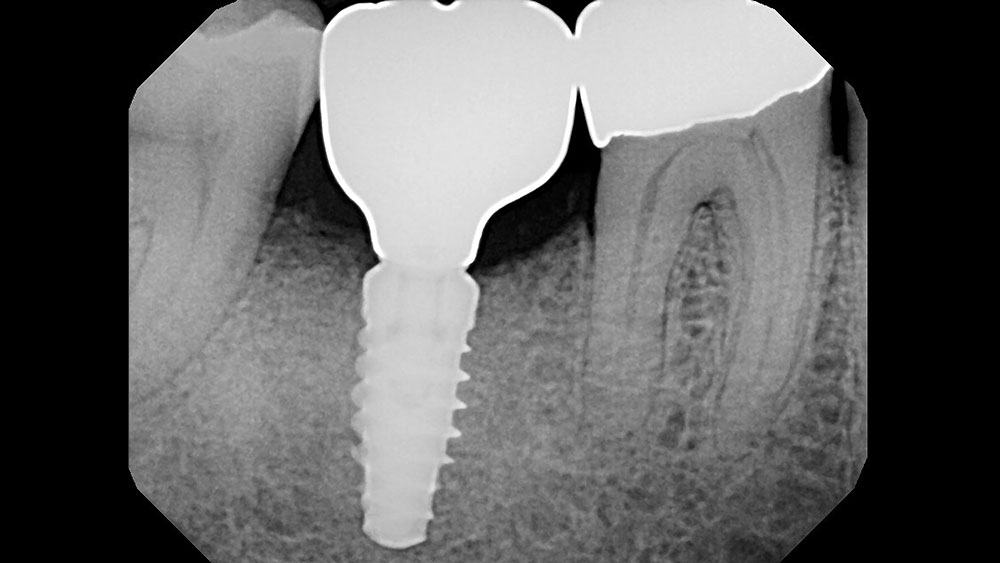

Following well-established clinical research methods, bone loss was measured as the distance from the implant shoulder to the first contact of bone to implant, from both the mesial and distal sides.

Figures 1a, 1b: Calibration of the bone loss measurements was determined by measuring the length of the implant (1a), or by measuring the diameter in cases where the implant apex was not visible (1b).